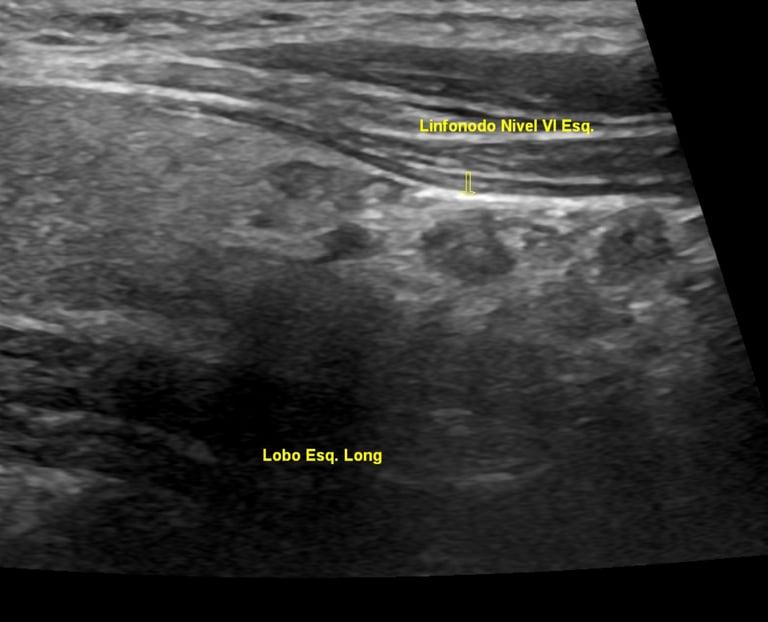

Nesse caso, você será submetido a um novo exame de ultrassonografia, mas desta vez com foco na obtenção da PAAF do nódulo em questão. O médico então irá puncionar o nódulo a ser avaliado com o auxílio da ultrassonografia, será coletado material suficiente para ser analisado em um microscópio por um patologista. Esse material contém somente algumas células do nódulo, estas podem ser células neoplásicas ou não, podem ser ainda células normais, da glândula tireoide ou ainda, pode não ter sido coletado nada, a não ser material hemático (sangue) sem utilização para estudo.